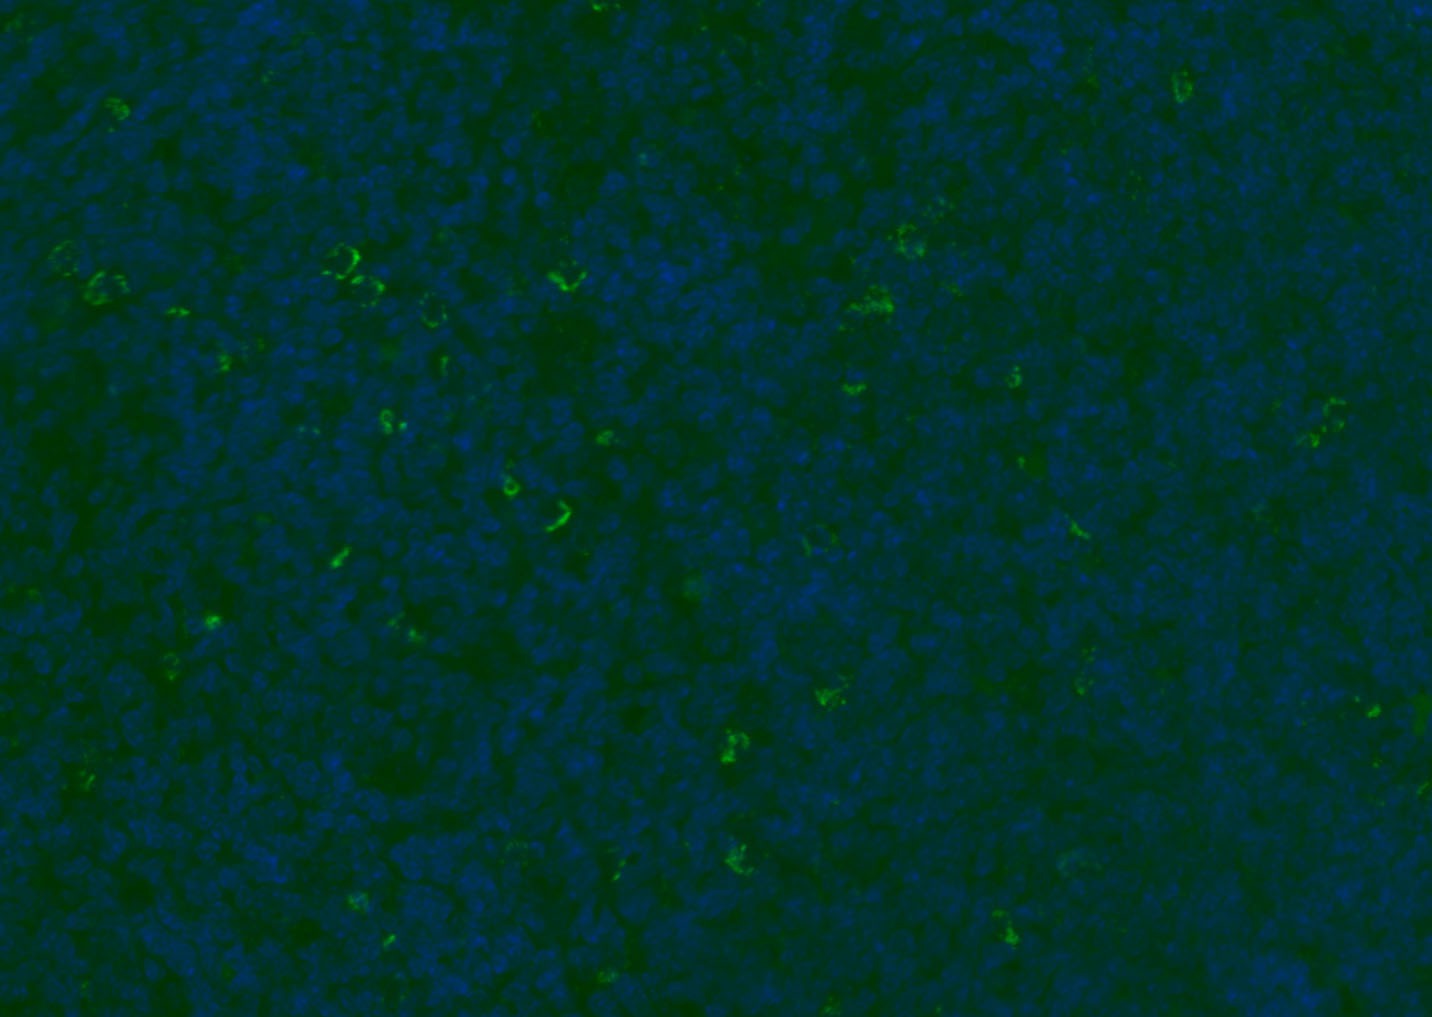

| Verified Activity | 1. Tissue/cell: human lung carcinoma;4% Paraformaldehyde-fixed and paraffin-embedded; Antigen retrieval: citrate buffer (0.01M, pH6.0), Boiling bathing for 15 min; Blocking buffer (normal goat serum) at 37°C for 20 min; Incubation: Anti-CD8 Polyclonal Antibody, Unconjugated (TMAB-00392) 1:200, overnight at 4°C; The secondary antibody was Goat Anti-Rabbit IgG, Cy3 conjugated used at 1:200 dilution for 40 minutes at 37°C. DAPI (5 μg/ml,blue) was used to stain the cell nucleus. 2. Paraformaldehyde-fixed, paraffin embedded (mouse lymphoid); Antigen retrieval by boiling in sodium citrate buffer (pH6.0) for 15 min; Blocking buffer (normal goat serum) at 37°C for 30 min; Antibody incubation with (CD8B) Polyclonal Antibody, Unconjugated (TMAB-00392) at 1:200 overnight at 4°C, followed by a conjugated Goat Anti-Rabbit IgG antibody for 90 minutes, and DAPI for nucleus staining. 3. Paraformaldehyde-fixed, paraffin embedded (rat spleen); Antigen retrieval by boiling in sodium citrate buffer (pH6.0) for 15 min; Blocking buffer (normal goat serum) at 37°C for 30 min; Antibody incubation with (CD8B) Polyclonal Antibody, Unconjugated (TMAB-00392) at 1:200 overnight at 4°C, followed by a conjugated Goat Anti-Rabbit IgG antibody for 90 minutes, and DAPI for nucleus staining. 4. Paraformaldehyde-fixed, paraffin embedded (mouse thymus); Antigen retrieval by boiling in sodium citrate buffer (pH6.0) for 15 min; Blocking buffer (normal goat serum) at 37°C for 30 min; Antibody incubation with (CD8B) Polyclonal Antibody, Unconjugated (TMAB-00392) at 1:200 overnight at 4°C, followed by a conjugated Goat Anti-Rabbit IgG antibody for 90 minutes, and DAPI for nucleus staining. 5. Paraformaldehyde-fixed, paraffin embedded (rat lymphoid); Antigen retrieval by boiling in sodium citrate buffer (pH6.0) for 15 min; Blocking buffer (normal goat serum) at 37°C for 30 min; Antibody incubation with (CD8B) Polyclonal Antibody, Unconjugated (TMAB-00392) at 1:200 overnight at 4°C, followed by a conjugated Goat Anti-Rabbit IgG antibody for 90 minutes, and DAPI for nucleus staining. 6. Paraformaldehyde-fixed, paraffin embedded (rat thymus); Antigen retrieval by boiling in sodium citrate buffer (pH6.0) for 15 min; Blocking buffer (normal goat serum) at 37°C for 30 min; Antibody incubation with (CD8B) Polyclonal Antibody, Unconjugated (TMAB-00392) at 1:200 overnight at 4°C, followed by a conjugated Goat Anti-Rabbit IgG antibody for 90 minutes, and DAPI for nucleus staining. 7. Paraformaldehyde-fixed, paraffin embedded (human tonsil); Antigen retrieval by boiling in sodium citrate buffer (pH6.0) for 15 min; Blocking buffer (normal goat serum) at 37°C for 30 min; Antibody incubation with (CD8B) Polyclonal Antibody, Unconjugated (TMAB-00392) at 1:200 overnight at 4°C, followed by a conjugated Goat Anti-Rabbit IgG antibody for 90 minutes, and DAPI for nucleus staining. 8. Paraformaldehyde-fixed, paraffin embedded (mouse lymphoid); Antigen retrieval by boiling in sodium citrate buffer (pH6.0) for 15 min; Blocking buffer (normal goat serum) at 37°C for 30 min; Antibody incubation with (CD8B) Polyclonal Antibody, Unconjugated (TMAB-00392) at 1:200 overnight at 4°C, followed by a conjugated Goat Anti-Rabbit IgG antibody for 90 minutes, and DAPI for nucleus staining. 9. Paraformaldehyde-fixed, paraffin embedded (rat thymus); Antigen retrieval by boiling in sodium citrate buffer (pH6.0) for 15 min; Blocking buffer (normal goat serum) at 37°C for 30 min; Antibody incubation with (CD8B) Polyclonal Antibody, Unconjugated (TMAB-00392) at 1:200 overnight at 4°C, followed by a conjugated Goat Anti-Rabbit IgG antibody for 90 minutes, and DAPI for nucleus staining. 10. Paraformaldehyde-fixed, paraffin embedded (human tonsil); Antigen retrieval by boiling in sodium citrate buffer (pH6.0) for 15 min; Blocking buffer (normal goat serum) at 37°C for 30 min; Antibody incubation with (CD8B) Polyclonal Antibody, Unconjugated (TMAB-00392) at 1:200 overnight at 4°C, followed by a conjugated Goat Anti-Rabbit IgG antibody for 90 minutes, and DAPI for nucleus staining. 11. Paraformaldehyde-fixed, paraffin embedded (mouse spleen); Antigen retrieval by boiling in sodium citrate buffer (pH6.0) for 15 min; Blocking buffer (normal goat serum) at 37°C for 30 min; Antibody incubation with (CD8B) Polyclonal Antibody, Unconjugated (TMAB-00392) at 1:200 overnight at 4°C, followed by a conjugated Goat Anti-Rabbit IgG antibody for 90 minutes, and DAPI for nucleus staining. 12. Paraformaldehyde-fixed, paraffin embedded (rat lymphoid); Antigen retrieval by boiling in sodium citrate buffer (pH6.0) for 15 min; Blocking buffer (normal goat serum) at 37°C for 30 min; Antibody incubation with (CD8B) Polyclonal Antibody, Unconjugated (TMAB-00392) at 1:200 overnight at 4°C, followed by a conjugated Goat Anti-Rabbit IgG antibody for 90 minutes, and DAPI for nucleus staining. 13. Paraformaldehyde-fixed, paraffin embedded (Rat lymphoid); Antigen retrieval by boiling in sodium citrate buffer (pH6.0) for 15 min; Blocking buffer (normal goat serum) at 37°C for 30 min; Antibody incubation with (CD8B) Polyclonal Antibody, Unconjugated (TMAB-00392) at 1:100 overnight at 4°C, followed by a conjugated Goat Anti-Rabbit IgG antibody for 90 minutes, and DAPI for nucleus staining. 14. Paraformaldehyde-fixed, paraffin embedded (mouse thymus); Antigen retrieval by boiling in sodium citrate buffer (pH6.0) for 15 min; Blocking buffer (normal goat serum) at 37°C for 30 min; Antibody incubation with (CD8B) Polyclonal Antibody, Unconjugated (TMAB-00392) at 1:100 overnight at 4°C, followed by a conjugated Goat Anti-Rabbit IgG antibody for 90 minutes, and DAPI for nucleus staining. 15. Paraformaldehyde-fixed, paraffin embedded (mouse spleen); Antigen retrieval by boiling in sodium citrate buffer (pH6.0) for 15 min; Blocking buffer (normal goat serum) at 37°C for 30 min; Antibody incubation with (CD8B) Polyclonal Antibody, Unconjugated (TMAB-00392) at 1:100 overnight at 4°C, followed by a conjugated Goat Anti-Rabbit IgG antibody for 90 minutes, and DAPI for nucleus staining. 16. Paraformaldehyde-fixed, paraffin embedded (rat spleen); Antigen retrieval by boiling in sodium citrate buffer (pH6.0) for 15 min; Blocking buffer (normal goat serum) at 37°C for 30 min; Antibody incubation with (CD8B) Polyclonal Antibody, Unconjugated (TMAB-00392) at 1:100 overnight at 4°C, followed by a conjugated Goat Anti-Rabbit IgG antibody for 90 minutes, and DAPI for nucleus staining. 17. Paraformaldehyde-fixed, paraffin embedded (rat thymus); Antigen retrieval by boiling in sodium citrate buffer (pH6.0) for 15 min; Blocking buffer (normal goat serum) at 37°C for 30 min; Antibody incubation with (CD8B) Polyclonal Antibody, Unconjugated (TMAB-00392) at 1:100 overnight at 4°C, followed by a conjugated Goat Anti-Rabbit IgG antibody for 90 minutes, and DAPI for nucleus staining. 18. Paraformaldehyde-fixed, paraffin embedded (human tonsil); Antigen retrieval by boiling in sodium citrate buffer (pH6.0) for 15 min; Blocking buffer (normal goat serum) at 37°C for 30 min; Antibody incubation with (CD8B) Polyclonal Antibody, Unconjugated (TMAB-00392) at 1:100 overnight at 4°C, followed by a conjugated Goat Anti-Rabbit IgG antibody for 90 minutes, and DAPI for nucleus staining. 19. Paraformaldehyde-fixed, paraffin embedded (mouse lymphoid); Antigen retrieval by boiling in sodium citrate buffer (pH6.0) for 15 min; Blocking buffer (normal goat serum) at 37°C for 30 min; Antibody incubation with (CD8B) Polyclonal Antibody, Unconjugated (TMAB-00392) at 1:100 overnight at 4°C, followed by a conjugated Goat Anti-Rabbit IgG antibody for 90 minutes, and DAPI for nucleus staining. ![]() ![]() ![]() ![]() ![]() ![]() ![]() ![]() ![]() ![]() ![]() ![]() ![]() ![]() ![]() ![]() ![]() ![]() ![]() |